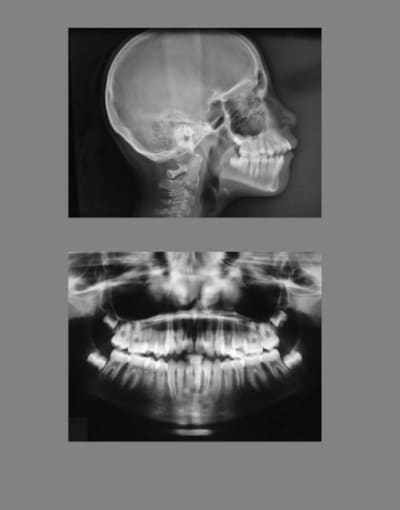

voici la Télé-Rx . de départ et la Télé-Rx. de fin de traitement

@+ Bjc.

T l  radio 1 et 2  jjd83f - Eugenol

T l  radio 1 et 2 agrandissement bfj76c - Eugenol